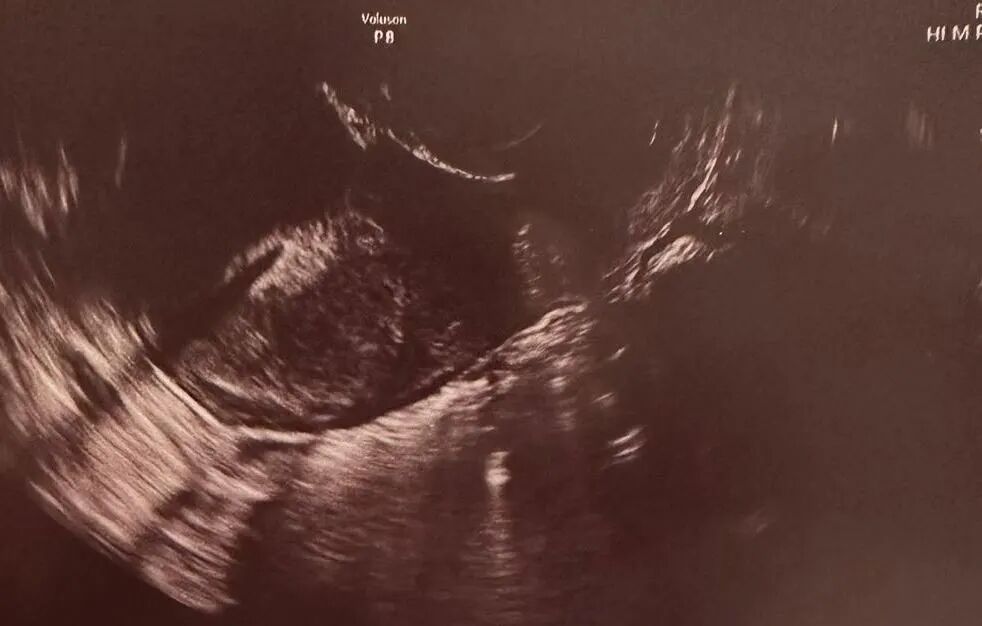

在爱妈B的悉心照料和监护下,怀孕进程一切顺利,宝宝已经健康成长到19周,期待下次的更新。